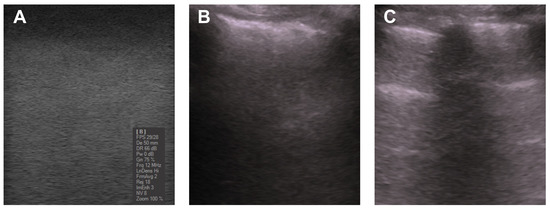

3.1. Ultrasound Characterization